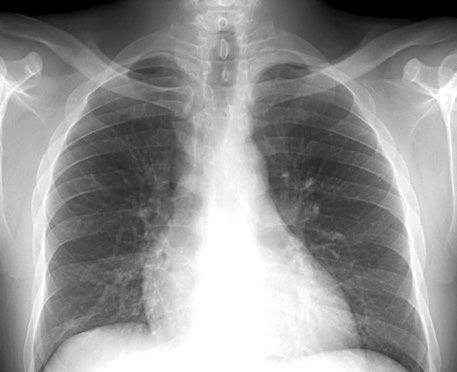

Asimetría de las partes blandas en Ca. de mama

Recidiva local Afectación de la piel